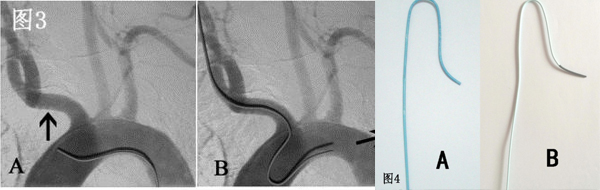

目前经桡动脉全脑血管造影通常选用的导管为西蒙造影导管,依据导管外形尺寸的大小分为三种型号,其中II-III型管均可被用于经桡动脉全脑血管造影(图4 A、B)。 西蒙造影导管的形状是按照经股动脉入路设计的,第一个弯在导管远端越过主动脉弓后可骑跨在主动脉弓上作为支点,而第二个弯曲则引导导管头端向上翘起,可选择性的进入无名动脉、左颈总动脉或左锁骨下动脉其中的任何一支血管(图3A)。 但是,在经桡动脉入路时,导管的第一弯曲无法骑跨在主动脉弓上,导管的第二弯曲引导的导管末端方向向下,这与脑主要血管的开口方向相反(图3B)。

因此, 需使用西蒙管的反勾技术(使导管扭曲呈“8”字形而不是导管原塑性的形状,使得导管末端的方向朝上)才能实现血管的超选(图5),这造成导管的操作困难